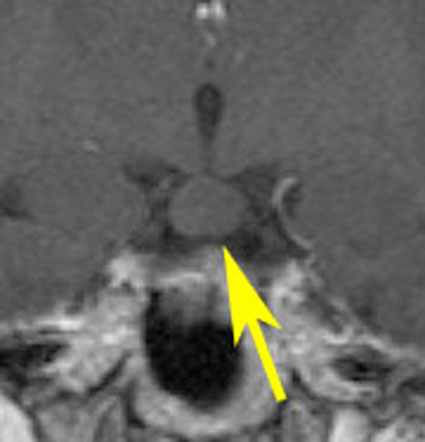

少年期に難治性の発作を生じて悪化しました,これを有茎 pedunculated とするかどうか微妙なところです

幼児期にgelastic seizureで発症